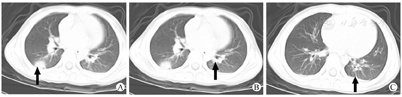

完善术前准备后拟行腹腔镜下阑尾切除术。术前测量体温时,发现患儿体温达38℃,手术医生见患儿母亲神情紧张,反复追问病史,患儿母亲诉患儿祖母已临床诊断为新型冠状病毒肺炎,正在隔离治疗中。患儿曾于2020年1月24日(除夕夜)与其祖母吃年夜饭时接触,后未再接触。考虑患儿为新型冠状病毒肺炎患者密切接触者,有发热症状,不能排除新型冠状病毒感染,立即予以安排单间隔离,同时通知手术室、麻醉科,所有接触医务人员均加强防护(穿防护服、佩戴护目镜、医用防护口罩、鞋套等)。密切接触人员单间隔离,病区内全部患儿及家属戴口罩和加强手卫生防护。完善准备工作后,患儿于2020年2月4日晚20点40分在喉罩全身麻醉下行腹腔镜下阑尾切除术,术中见阑尾化脓,中段穿孔,右下腹局限性腹膜炎,手术顺利。术后给予抗感染、补液等对症支持治疗。患儿2020年2月5日晨出现咳嗽、低热。考虑患儿系疑似新型冠状病毒肺炎,进一步行胸部CT平扫提示右肺下叶背段见一类圆形致密影,边缘略呈磨玻璃样改变,截面大小约12 mm×20 mm(图1A);右肺上叶后段近胸膜处见小片状淡薄影,左肺下叶局部见条状影(图1B);双侧胸膜下见弧形致密影(图1C)。影像学诊断:病毒性肺炎,建议进行病原学检查,短期复查。患儿随即转入传染病区疑似病房,行咽拭子2019新型冠状病毒(2019-nCoV)核酸检测,予以普米克及干扰素雾化、头孢哌酮抗感染治疗,并监测血氧饱和度。2020年2月6日患儿仍有咳嗽、发热,无胸闷气促,无呕吐、腹痛、腹泻;首次咽拭子核酸检测呈阴性。同时,患儿祖母于武汉市某医院住院治疗,查得咽拭子病毒核酸检测阳性。2020年2月6日第2次取患儿咽拭子标本行2019-nCoV核酸检测,结果为阳性。2020年2月7日患儿咳嗽较前稍缓解,仍有发热,最高体温39℃,予以双氯芬酸钠栓纳肛后可缓慢降至正常,大便黄稀,尿量可;同时行第3次咽拭子2019-nCoV核酸检测。2020年2月8日患儿仍有轻微咳嗽,间断发热,最高体温39℃。第3次咽拭子核酸检测再次阳性,间隔24 h以上2次新型冠状病毒核酸检测阳性,患儿明确诊断新型冠状病毒肺炎,随即转入传染病区确诊病区治疗。2020年2月10日患儿精神、食欲较前变好,轻微咳嗽,未再发热,未诉胸闷及乏力,无呕吐、腹痛、腹泻,大小便正常,咽拭子2019-nCoV核酸检测阴性。2020年2月12日患儿再次行咽拭子2019-nCoV核酸检测阴性。2020年2月14日患儿精神反应、食欲明显好转,无发热,无咳嗽及咳痰,无胸闷、气促,无呕吐及腹泻,大小便正常。患儿临床症状好转,连续2次复查咽拭子2019-nCoV核酸检测阴性,达出院标准,予出院。嘱注意饮食,避免受凉及再感染,居家隔离2周。

低龄儿童多存在体格检查不配合、描述不清晰、呼吸道症状体征不明显等问题,尤其是以急腹症为首发表现且合并2019-nCoV感染的患儿,使得疫情下合理安排手术更加困难。有专家建议常规行肺部CT扫描来筛查新型冠状病毒肺炎。在成人,新型冠状病毒肺炎患者肺部CT具有特征性的片状阴影或毛玻璃样改变[9]。但儿童患者肺部CT表现没有成人典型,病灶相对局限,弥漫性分布相对较少,部分呈淡薄云雾状[10]。本例CT表现为局限性病灶,仅在病灶边缘略呈毛玻璃样改变。病毒核酸检测和高通量测序对于确诊新型冠状病毒肺炎至关重要,但在临床实际操作过程中假阴性过高、耗时长。在急诊情况下依靠常规核酸检测来确诊和排除新型冠状病毒感染不现实,只能严格把控急症手术指征,对怀疑感染病例按照疑似感染病例进行收治防护,并于后期尽早进行病原学检测明确诊断和治疗。